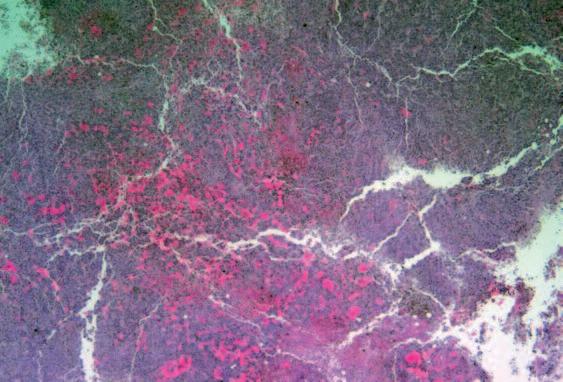

Immagine al microscopio di cellule leucemiche. Le sfere rosse del pacmen rappresentano gli enzimi collagenasi.

Questo vale anche per le cellule leucemiche. Una caratteristica di questa forma di tumore del sangue è l’eccesso di produzione di globuli bianchi, i pazienti affetti da leucemia muoiono principalmente, perché queste cellule bloccano la circolazione del sangue. In molti casi i leucemici muoiono per il cedimento di vari organi, in particolare ‘gli organi filtro’: il fegato e la milza. Milioni di globuli bianchi invadono questi organi attraverso il flusso sanguigno. Queste cellule cancerose producono immense quantità di enzimi che digeriscono il collagene, digerendo letteralmente questi organi dall'interno.

La foto nella pagina a fianco mostra una sezione trasversale al microscopio del fegato di un paziente con ‘leucemia linfatica’. Ciascuno dei piccoli puntini viola nella foto è un globulo bianco (in questo caso linfocita) che ha invaso il tessuto del fegato (aree rosa).

Considerando l’enorme quantità di questi puntini viola e il numero di enzimi che assimilano il collagene che ciascuno produce, è facile prevedere l’ingente distruzione del tessuto connettivo e il danno apportato all’organo da questo tipo di cancro.

La leucemia è un buon esempio di come la comprensione dei meccanismi delle cellule tumorali, la produzione di enzimi che digeriscono il collagene da parte dei globuli bianchi, per poter studiare terapie efficaci.

Immagine al microscopio della leucemia linfatica

Globuli bianchi affetti di cancro (linfociti) invadono il fegato L’enorme quantità di collagenasi prodotte da queste cellule distruggono l’organo e causano insufficienza epatica.